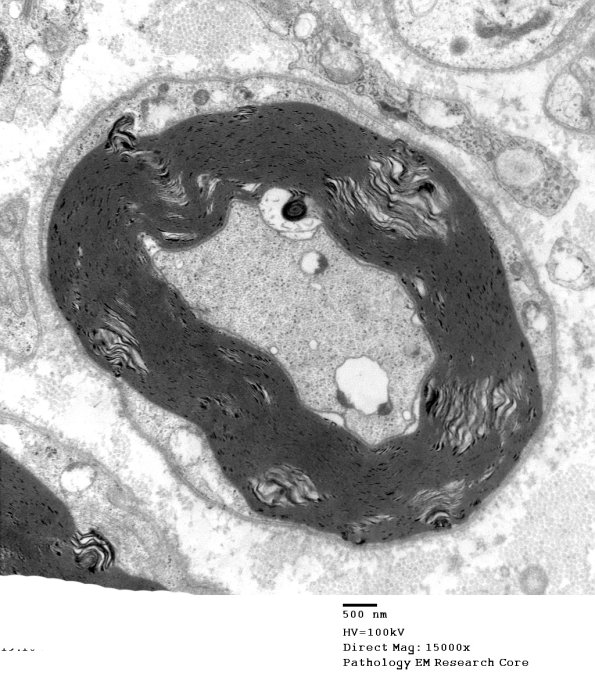

Washington University Experience | PERIPHERAL NEUROPATHY | 0 PNS ARTIFACTS | 7B1 Artifact, separation myelin, Amiodarone (B1899)_005a - Copy

Small splits in the myelin sheath itself are common alterations thought to reflect problems with dehydration of the specimen during processing. (electron micrograph)